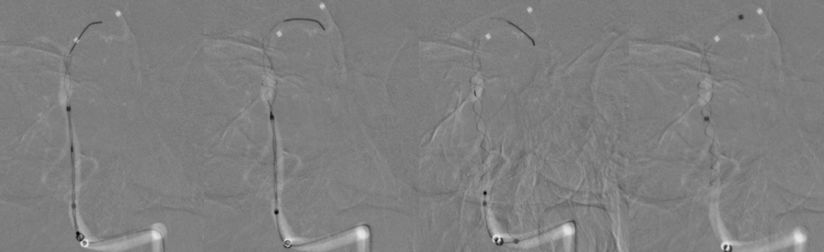

本院DSA:基底动脉巨大夹层动脉瘤,双侧后交通动脉未见明显开放(图6)。

图6

本院 DSA三维血管重建(2019-10-10)显示:基底动脉巨大夹层动脉瘤(图7)。

图7

1、患者全身麻醉,右侧股动脉穿刺置入8F动脉鞘,5F中间导管携带6F长鞘超选入左侧椎动脉,行造影及三维旋转寻找最佳工作角度(图8)。

图8

2、调整至合适的工作角度后,撤出5F中间导管,将5F Navien 通过6F长鞘置入左侧V3段。路图引导下由2 m Synchro-14微导丝将T-track支架微导管超选进左侧大脑后动脉P2段(图9)。

图9

3、多个投射角度辅助下,将一枚3x35 mm的Tubridge支架经T-track支架微导管缓慢释放(图10)。

图10

4、支架完全释放后造影可见支架完全覆盖动脉瘤,贴壁良好,载瘤动脉及支架覆盖的双侧AICA及右侧椎动脉通畅(图11)。

图11